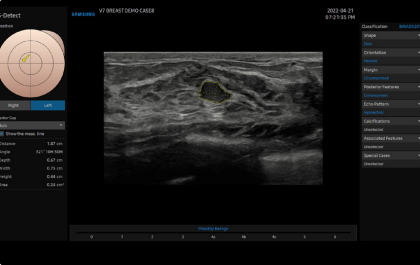

El ecógrafo Samsung V7 redefine la excelencia en diagnóstico por ultrasonido al combinar diseño ergonómico, flujo de trabajo optimizado y una arquitectura de imagen avanzada. Equipado con Crystal Architecture™, CrystalBeam™ y CrystalLive™, el V7 ofrece imágenes nítidas, detalladas y consistentes que mejoran la confianza diagnóstica en múltiples especialidades.

Diseñado para hospitales y clínicas que buscan un ecógrafo de alto rendimiento, el V7 proporciona herramientas inteligentes con Intelligent Assist™ y tecnologías de visualización avanzadas como ShadowHDR™, ClearVision™ y MV-Flow™, ofreciendo resultados precisos en menos tiempo.

Redefiniendo la imagen con Crystal Architecture™

El Samsung V7 incorpora Crystal Architecture™, una plataforma de imagen avanzada que integra CrystalBeam™ y CrystalLive™, optimizada por sondas S-Vue™. Esta arquitectura permite imágenes más limpias, nítidas y de alta resolución, mejorando la confianza diagnóstica en obstetricia, ginecología, cardiología y aplicaciones generales.

CrystalBeam™ mejora la resolución y uniformidad de imagen mediante formación avanzada de haces, incluso en estructuras profundas o difíciles de visualizar.

CrystalLive™ ofrece renderizado 3D y procesamiento de señal de color mejorados, facilitando diagnósticos complejos y optimizando el flujo de trabajo.